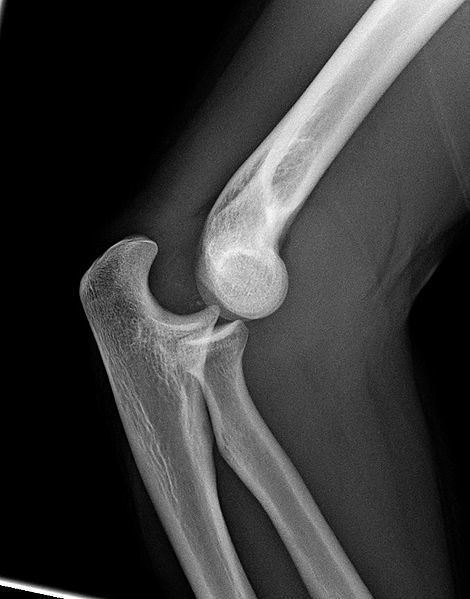

What would you see on x-ray if pt has elbow dislocation?

Loss of radiocapitellar and ulnotrochlear congruence